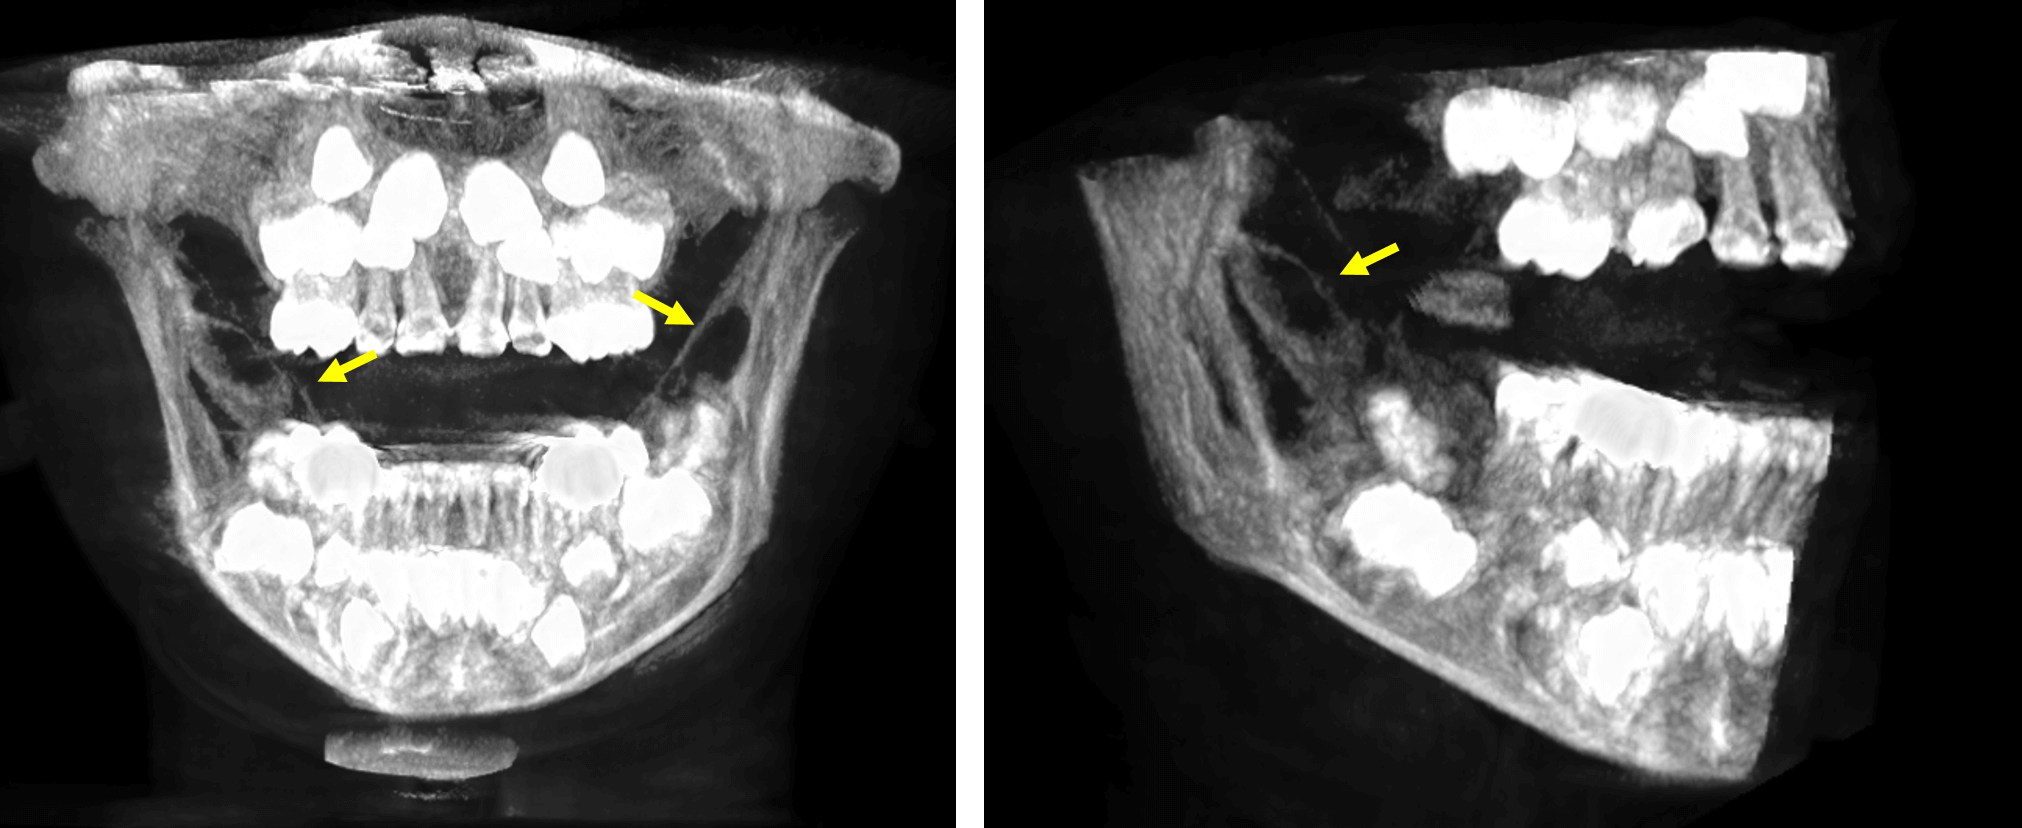

Fig.5

En cortes axiales (Fig.5) se observa también el compromiso de las tablas óseas en ambas ramas ascendentes, condicionando la leve expansión, adelgazamiento y probable erosión de las corticales óseas.

Fig.6

En las imágenes tridimensionales (Fig.6) se observa los signos tomográficos anteriormente descritos en ambos lados del maxilar inferior. Se consideran signos tomográficos de una lesión de aparente naturaleza tumoral.